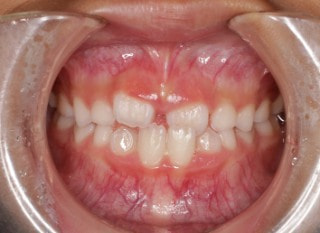

治療前